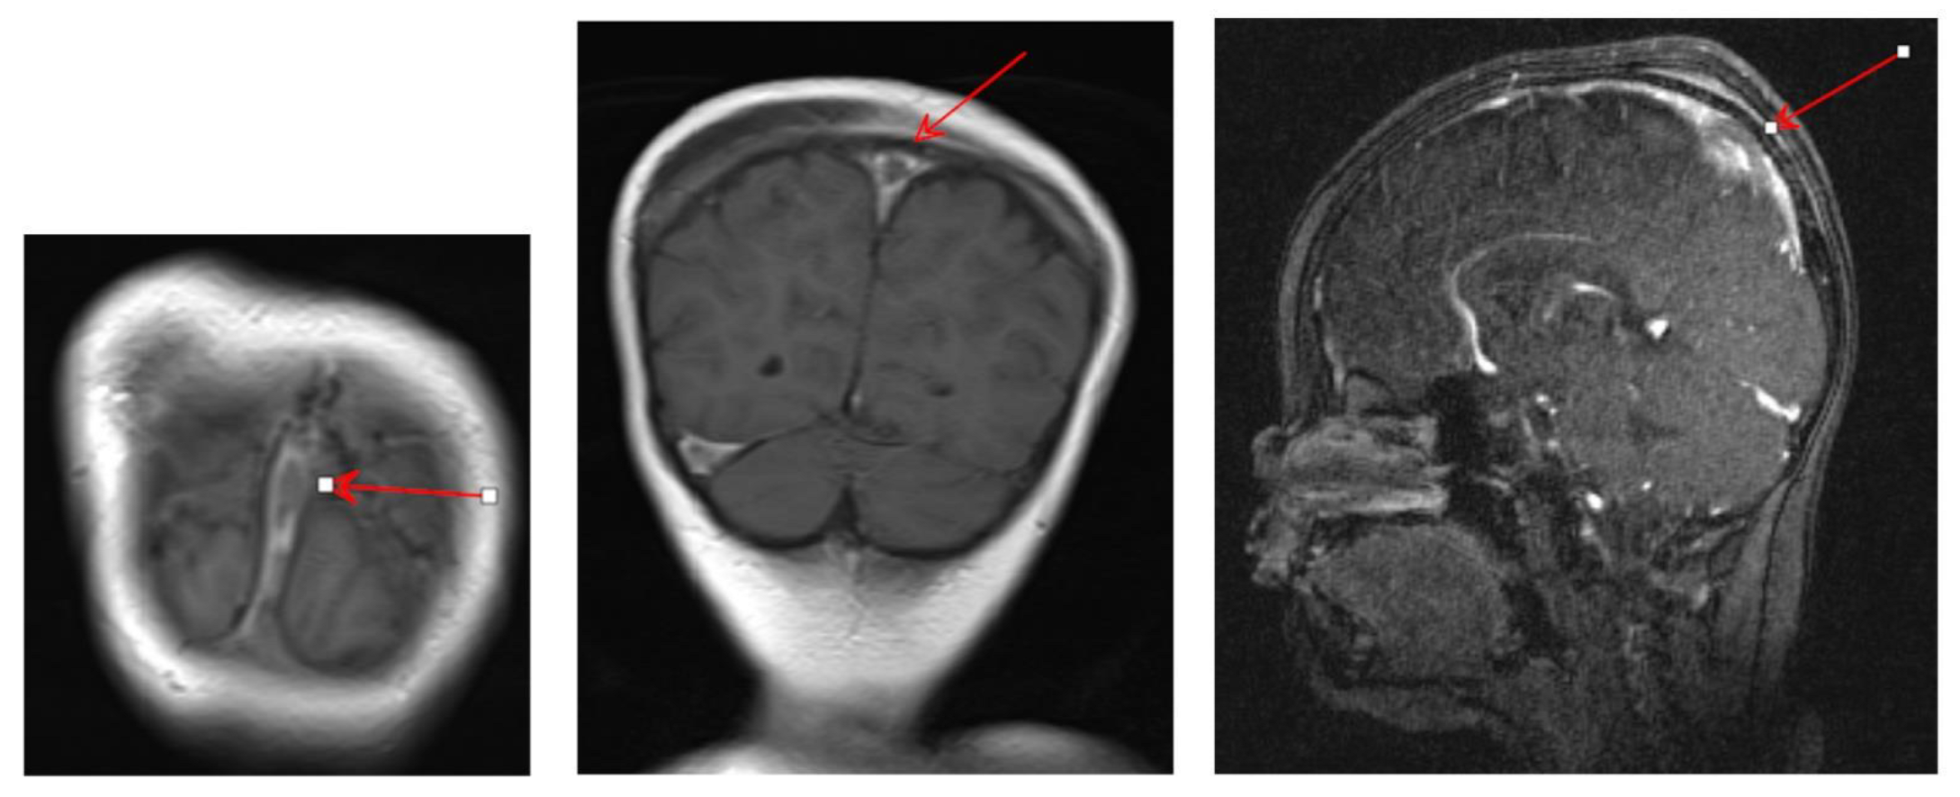

2. Case Presentation